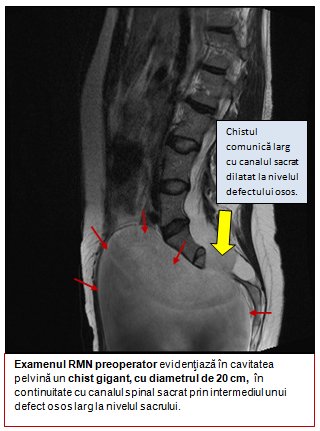

Florentina are 34 de ani şi în urmă cu 4 luni a început să prezinte dificultate la urinare, febră şi repetate infecţii urinare grave la nivelul rinichilor, care au necesitat tratament antibiotic prelungit. Ecografia aparatului urinar a arătat o dilataţie a căilor urinare din interiorul rinichilor şi a ureterelor, datorită compresiei produse de un chist voluminos localizat în cavitatea pelvină, cu diametru de 20 cm, care conţinea 2000 ml de lichid.

Investigaţii imagistice detaliate, RMN şi CT, au permis evidenţierea unui meningocel sacrat anterior gigant. Acesta reprezintă extensia în cavitatea pelvină a nervilor şi a meningelui spinal, ca urmare a unei anomalii complexe de dezvoltare a porţiunii terminale a coloanei vertebrale, în care câteva dintre vertebre se dezvoltă incomplet. Porţiunea terminală a coloanei vertebrale este fixă, fiind formată din vertebrele sacrate fuzionate, de unde denumirea de os sacru.

În interiorul osului sacru se continuă canalul spinal, care conţine sacul meningeal şi fluidul spinal în care se găsesc nervii sacraţi, care asigură controlul vezicii urinare, al sfincterului anal şi sensibilitatea din regiunea bazinului şi a organelor genitale.